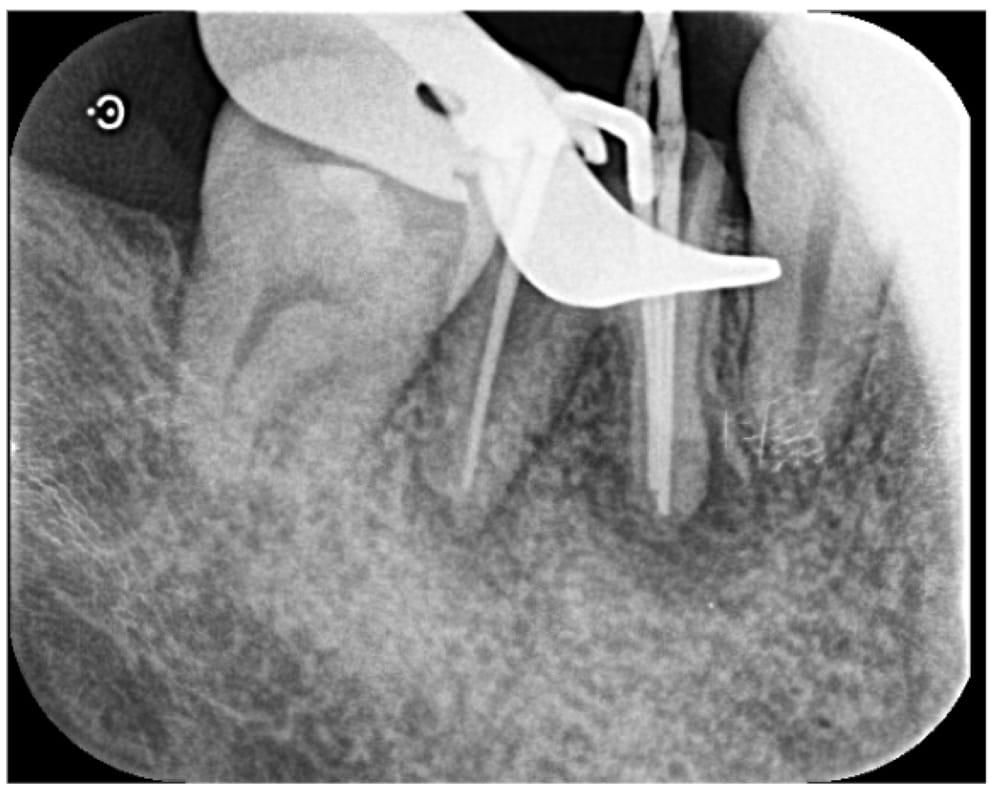

根管内の感染を取り除くため、ニッケルチタンファイルを使用して根管内を形成後、抗菌作用がある次亜塩素酸ナトリウム溶液でしっかりと洗浄しました。根管内には水酸化カルシウムを貼薬し、外部からの細菌漏洩を防ぐために緊密に仮封し一度目の治療を終了しました。